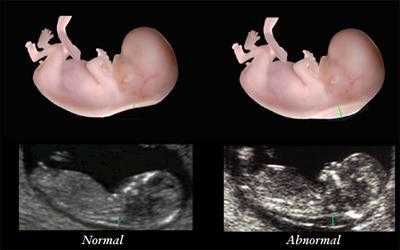

ΠΡΠΈ ΠΏΡΠΎΠ²Π΅Π΄Π΅Π½ΠΈΠΈ Π£ΠΠ Π΄ΠΎΠΊΡΠΎΡ ΠΎΠ±ΡΠ°ΡΠ°Π΅Ρ Π²Π½ΠΈΠΌΠ°Π½ΠΈΠ΅ Π½Π° Π²ΠΎΡΠΎΡΠ½ΠΈΡΠΊΠΎΠ²ΡΡ Π·ΠΎΠ½Ρ. ΠΠ΅Π»ΠΎ Π² ΡΠΎΠΌ, ΡΡΠΎ ΠΏΡΠΈ Π½Π°Π»ΠΈΡΠΈΠΈ ΡΠΈΠ½Π΄ΡΠΎΠΌΠ° ΠΠ°ΡΠ½Π° Π½Π° ΡΠ΅Π΅ ΠΎΠ±ΡΠ°Π·ΡΠ΅ΡΡΡ ΡΠΊΠ»Π°Π΄ΠΊΠ°, ΡΠ°ΠΊ ΠΊΠ°ΠΊ Π² Π²ΠΎΡΠΎΡΠ½ΠΈΡΠΊΠΎΠ²ΠΎΠΉ Π·ΠΎΠ½Π΅ Π½Π°ΠΊΠ°ΠΏΠ»ΠΈΠ²Π°Π΅ΡΡΡ ΡΡΠ΅Π·ΠΌΠ΅ΡΠ½ΠΎΠ΅ ΠΊΠΎΠ»ΠΈΡΠ΅ΡΡΠ²ΠΎ ΠΆΠΈΠ΄ΠΊΠΎΡΡΠΈ.Π ΠΈΡΠΊΠΈ ΠΏΡΠΈ Π΄ΠΎΠΏΠΎΠ»Π½ΠΈΡΠ΅Π»ΡΠ½ΡΡ ΠΌΠ΅ΡΠΎΠ΄Π°Ρ Π΄ΠΈΠ°Π³Π½ΠΎΡΡΠΈΠΊΠΈ

- Π£ΠΠ. ΠΠΏΠ΅ΡΠ²ΡΠ΅ Π΄ΠΎΠ»ΠΆΠ½ΠΎ ΠΏΡΠΎΠ²ΠΎΠ΄ΠΈΡΡΡΡ Π² ΠΏΠ΅ΡΠΈΠΎΠ΄ ΠΎΡ 11 Π΄ΠΎ 13 Π½Π΅Π΄Π΅Π»ΠΈ. Π ΡΠ°ΠΊΠΎΠΌ ΡΠ»ΡΡΠ°Π΅ Π±ΡΠ΄Π΅Ρ ΠΈΡΡΠ»Π΅Π΄ΠΎΠ²Π°ΡΡΡΡ Π²ΠΎΡΠΎΡΠ½ΠΈΠΊΠΎΠ²ΠΎΠ΅ ΠΏΡΠΎΡΡΡΠ°Π½ΡΡΠ²ΠΎ ΠΌΠ°Π»ΡΡΠ°, ΡΡΠΎ ΠΈ Π΄Π°ΡΡ Π²ΠΎΠ·ΠΌΠΎΠΆΠ½ΠΎΡΡΡ ΡΠΊΠ°Π·Π°ΡΡ ΠΎ ΡΠΎΠΌ, Π΅ΡΡΡ Π»ΠΈ Π΄Π°Π½Π½Π°Ρ ΠΏΠ°ΡΠΎΠ»ΠΎΠ³ΠΈΡ Ρ ΡΠ΅Π±Π΅Π½ΠΊΠ° (Π½Π° ΡΠ»ΡΡΡΠ°Π·Π²ΡΠΊΠΎΠ²ΠΎΠΌ ΠΈΡΡΠ»Π΅Π΄ΠΎΠ²Π°Π½ΠΈΠΈ ΠΌΠΎΠΆΠ΅Ρ Π±ΡΡΡ Π²ΠΈΠ΄Π½Π° Π»ΠΈΡΠ½ΡΡ ΡΠΊΠ»Π°Π΄ΠΊΠ° ΠΈΠ»ΠΈ ΠΆΠ΅ Π΄ΠΎΠΏΡΡΡΠΈΠΌΠ°Ρ ΡΠΎΠ»ΡΠΈΠ½Π° Π²ΠΎΡΠΎΡΠ½ΠΈΠΊΠΎΠ²ΠΎΠΉ Π·ΠΎΠ½Ρ Π±ΡΠ΄Π΅Ρ Π±ΠΎΠ»ΡΡΠ΅ 3 ΠΌΠΌ)

ΠΠΏΡΠ΅Π΄Π΅Π»ΠΈΡΡ ΡΠΈΠ½Π΄ΡΠΎΠΌ ΠΠ°ΡΠ½Π° ΠΌΠΎΠΆΠ½ΠΎ Π΄Π°ΠΆΠ΅ Π½Π° ΡΠ°Π½Π½ΠΈΡ ΡΡΠΎΠΊΠ°Ρ Π±Π΅ΡΠ΅ΠΌΠ΅Π½Π½ΠΎΡΡΠΈ. ΠΠ±ΡΡΠ½ΠΎ ΠΏΠ΅ΡΠ²ΡΠΌ ΡΡΠ°ΠΏΠΎΠΌ Π΄ΠΈΠ°Π³Π½ΠΎΡΡΠΈΠΊΠΈ ΡΠ²Π»ΡΠ΅ΡΡΡ ΡΠ»ΡΡΡΠ°Π·Π²ΡΠΊΠΎΠ²ΠΎΠ΅ ΠΈΡΡΠ»Π΅Π΄ΠΎΠ²Π°Π½ΠΈΠ΅. ΠΠ½ΠΎ Π²ΡΠΏΠΎΠ»Π½ΡΠ΅ΡΡΡ Π² 11-13 Π½Π΅Π΄Π΅Π»Ρ ΠΈ ΠΏΠΎΠ·Π²ΠΎΠ»ΡΠ΅Ρ Π²ΡΡΠ²ΠΈΡΡ ΠΊΠΎΡΠ²Π΅Π½Π½ΡΠ΅ ΠΏΡΠΈΠ·Π½Π°ΠΊΠΈ Π³Π΅Π½Π΅ΡΠΈΡΠ΅ΡΠΊΠΎΠ³ΠΎ ΠΎΡΠΊΠ»ΠΎΠ½Π΅Π½ΠΈΡ. ΠΠ΄Π½ΠΈΠΌ ΠΈΠ· Π½ΠΈΡ ΡΠ²Π»ΡΠ΅ΡΡΡ ΡΠΎΠ»ΡΠΈΠ½Π° Π²ΠΎΡΠΎΡΠ½ΠΈΠΊΠΎΠ²ΠΎΠ³ΠΎ ΠΏΡΠΎΡΡΡΠ°Π½ΡΡΠ²Π°. ΠΡΠ»ΠΈ ΠΎΠ½Π° ΠΏΡΠ΅Π²ΡΡΠ°Π΅Ρ 3 ΠΌΠΌ, Π΅ΡΡΡ Π²ΡΠ΅ ΠΎΡΠ½ΠΎΠ²Π°Π½ΠΈΡ ΠΏΡΠ΅Π΄ΠΏΠΎΠ»Π°Π³Π°ΡΡ ΡΠΈΠ½Π΄ΡΠΎΠΌ ΠΠ°ΡΠ½Π°. ΠΠΎΠΏΠΎΠ»Π½ΠΈΡΠ΅Π»ΡΠ½ΡΠΌ ΠΌΠ°ΡΠΊΠ΅ΡΠΎΠΌ ΡΠ²Π»ΡΠ΅ΡΡΡ Π²Π΅Π»ΠΈΡΠΈΠ½Π° ΠΊΠΎΡΡΠΈ Π½ΠΎΡΠ°. ΠΡΠ»ΠΈ ΠΊΠΎΡΡΡ ΠΎΡΡΡΡΡΡΠ²ΡΠ΅Ρ ΠΈΠ»ΠΈ ΠΈΠΌΠ΅Π΅Ρ Π½Π΅ΡΠΎΠΎΡΠ²Π΅ΡΡΡΠ²ΡΡΡΠΈΠΉ ΡΡΠΎΠΊΡ ΡΠ°Π·ΠΌΠ΅Ρ, ΡΡΠΎΠΈΡ ΠΏΡΠΎΠΉΡΠΈ ΡΠ³Π»ΡΠ±Π»Π΅Π½Π½ΠΎΠ΅ ΠΎΠ±ΡΠ»Π΅Π΄ΠΎΠ²Π°Π½ΠΈΠ΅. ΠΡΠ΅Π΄ΠΏΠΎΠ»ΠΎΠΆΠΈΡΡ Π½Π°Π»ΠΈΡΠΈΠ΅ ΡΠΈΠ½Π΄ΡΠΎΠΌΠ° ΠΠ°ΡΠ½Π° Ρ ΠΏΠ»ΠΎΠ΄Π° ΠΌΠΎΠΆΠ½ΠΎ ΠΏΠΎ ΡΠΊΡΠΈΠ½ΠΈΠ½Π³ΠΎΠ²ΠΎΠΌΡ ΠΈΡΡΠ»Π΅Π΄ΠΎΠ²Π°Π½ΠΈΡ ΠΊΡΠΎΠ²ΠΈ. ΠΠ³ΠΎ ΠΌΠΎΠΆΠ½ΠΎ ΠΏΡΠΎΠ²Π΅ΡΡΠΈ Π΄Π²Π°ΠΆΠ΄Ρ: Π² 10-13 Π½Π΅Π΄Π΅Π»Ρ ΠΈ Π² 16-18. ΠΠ΄Π½Π°ΠΊΠΎ Π΄Π°Π½Π½ΡΠ΅ ΡΠ΅ΡΡΡ ΡΠ°ΡΡΡΠΈΡΡΠ²Π°ΡΡ Π»ΠΈΡΡ Π²Π΅ΡΠΎΡΡΠ½ΠΎΡΡΡ ΡΠΎΠΆΠ΄Π΅Π½ΠΈΡ ΡΠ΅Π±Π΅Π½ΠΊΠ° Ρ Π³Π΅Π½Π΅ΡΠΈΡΠ΅ΡΠΊΠΈΠΌΠΈ ΠΎΡΠΊΠ»ΠΎΠ½Π΅Π½ΠΈΡΠΌΠΈ. Π‘ ΠΈΡ ΠΏΠΎΠΌΠΎΡΡΡ ΠΌΠΎΠΆΠ½ΠΎ Π»ΠΈΡΡ ΠΏΡΠ΅Π΄ΠΏΠΎΠ»ΠΎΠΆΠΈΡΡ, Π½ΠΎ Π½Π΅ ΡΡΡΠ°Π½ΠΎΠ²ΠΈΡΡ ΠΎΠΊΠΎΠ½ΡΠ°ΡΠ΅Π»ΡΠ½ΠΎ Π½Π°Π»ΠΈΡΠΈΠ΅ Ρ ΠΏΠ»ΠΎΠ΄Π° ΡΠΈΠ½Π΄ΡΠΎΠΌΠ° ΠΠ°ΡΠ½Π°.ΠΠ±ΡΠ°ΡΠΈΡΠ΅ΡΡ ΠΊ Π³Π΅Π½Π΅ΡΠΈΠΊΡ, Π΅ΡΠ»ΠΈ Π²Ρ Π²Ρ ΠΎΠ΄ΠΈΡΠ΅ Π² Π³ΡΡΠΏΠΏΡ ΡΠΈΡΠΊΠ° (Π²ΠΎΠ·ΡΠ°ΡΡ ΡΡΠ°ΡΡΠ΅ 35 Π»Π΅Ρ) ΠΏΠΎ ΡΠΎΠΆΠ΄Π΅Π½ΠΈΡ ΠΌΠ°Π»ΡΡΠ° Ρ ΡΠΈΠ½Π΄ΡΠΎΠΌΠΎΠΌ ΠΠ°ΡΠ½Π°. Π’Π°ΠΊΠΆΠ΅ ΠΏΠΎΠΊΠ°Π·Π°Π½ΠΈΡΠΌΠΈ Π΄Π»Ρ ΡΠ°ΠΊΠΎΠΉ ΠΊΠΎΠ½ΡΡΠ»ΡΡΠ°ΡΠΈΠΈ ΡΠ²Π»ΡΡΡΡΡ ΠΎΡΠΊΠ»ΠΎΠ½Π΅Π½ΠΈΡ Ρ ΠΏΠ»ΠΎΠ΄Π° ΠΏΠΎ ΡΠ΅Π·ΡΠ»ΡΡΠ°ΡΠ°ΠΌ ΡΠ·ΠΈ ΠΈ Π²ΡΡΠΎΠΊΠ°Ρ Π²Π΅ΡΠΎΡΡΠ½ΠΎΡΡΡ ΡΠΎΠΆΠ΄Π΅Π½ΠΈΡ Π±ΠΎΠ»ΡΠ½ΠΎΠ³ΠΎ ΡΠ΅Π±Π΅Π½ΠΊΠ°, ΡΠ°ΡΡΡΠΈΡΠ°Π½Π½Π°Ρ Π½Π° ΠΎΡΠ½ΠΎΠ²Π°Π½ΠΈΠΈ ΡΠΊΡΠΈΠ½ΠΈΠ½Π³ΠΎΠ²ΠΎΠ³ΠΎ ΠΈΡΡΠ»Π΅Π΄ΠΎΠ²Π°Π½ΠΈΡ.

ΠΠ΅ΡΠ²ΡΠ΅ ΠΏΡΠΈΠ·Π½Π°ΠΊΠΈ ΠΏΠ°ΡΠΎΠ»ΠΎΠ³ΠΈΠΈ ΠΏΡΠΈ Π£ΠΠ ΠΌΠΎΠ³ΡΡ Π±ΡΡΡ ΠΎΠ±Π½Π°ΡΡΠΆΠ΅Π½Ρ Π½Π° ΡΡΠΎΠΊΠ΅ Π² 14 Π½Π΅Π΄Π΅Π»Ρ.

- ΡΠΎΠ»ΡΠΈΠ½Π° Π²ΠΎΡΠΎΡΠ½ΠΈΠΊΠΎΠ²ΠΎΠ³ΠΎ ΠΏΡΠΎΡΡΡΠ°Π½ΡΡΠ²Π°, Π½Π°Π±Π»ΡΠ΄Π°Π΅ΠΌΠ°Ρ Π² 75% ΡΠ»ΡΡΠ°Π΅Π²;

- ΡΠΊΠΎΡΠΎΡΠ΅Π½Π½Π°Ρ Π½ΠΎΡΠΎΠ²Π°Ρ ΠΊΠΎΡΡΡ ΠΈΠ»ΠΈ Π΅Π΅ ΠΏΠΎΠ»Π½ΠΎΠ΅ ΠΎΡΡΡΡΡΡΠ²ΠΈΠ΅;